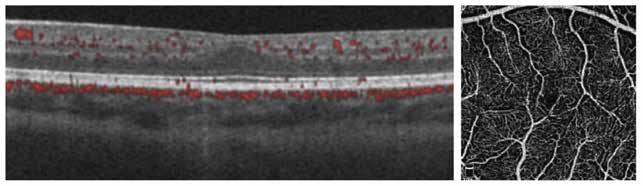

Figure 2. Multimodal imaging of right eye of a male diabetic patient affected by PDR and DME. 2A-B) UWF pseudocolor retinography (Optos Silverstone, Optos, UK) and corresponding magnification of macular region showing diffuse hard exudates and intraretinal hemorrages; 2C) OCT (Heidelberg Spectralis, Heidelberg Engineering Inc., Germany) displaying diffuse center-involving DME; 2D-E) Late phase UWF FA (Optos Silverstone, Optos, UK) and corresponding magnification of macular region presenting extense breakdown of BRB with perivascular leakage and non-perfusion areas, pooling effect compatible with MA and masking effect due to pre-retinal hemorrhages. Two leakage spots associated to possible NVs close to inferior vascular arcade; 2F) 3x3 B-scan OCT-A (Zeiss PLEX Elite 9000, Carl Zeiss, Germany) showing flow signal within pre-retinal NV.

Figure 3. Multimodal imaging of a male diabetic patient affected by PDR and DME that has already been treated by incomplete laser photocoagulation therapy. 3A) UWF pseudocolor retinography displaying hard exudates and intraretinal hemorrhages within vascular arcades and peripheral laser photocoagulation therapy; 3B) UWF SS-OCT showing focal center-involving DME; 3C) Late phase UWF FA (describing mild BRB disruption with 2 leakage areas compatible with NV along inferior vascular arcade; 3D) 15x15 En-face WF-SS-OCTA presenting FAZ enlargement, diffuse capillary drop-out and temporal mid-peripheral retinal nonperfusion areas, and two pathological vascular networks associated to NVs.

Figure 4. Multimodal imaging of a female diabetic patient affected by PDR that has already undergone complete laser photocoagulation treatment. 4A) UWF pseudocolor retinography showing complete laser photocoagulation treatment until vascular arcades; 4B-C) 12x12 and 4E-F) en-face WF-SS-OCTA of diabetic patient (4B, 4E) presenting FAZ enlargement, diffuse capillary drop-out and inferior mid-peripheral retinal nonperfusion areas, as compared to healthy patient (4C, 4F; 4D) Late phase UWF FA displaying diffuse BRB breakdwon, with perivascular leakage and non-perfusion areas.

5. Multimodal imaging of a

diabetic patient affected by

5A) UWF pseudocolor retinography showing some hard exudates within and outside vascular arcades; 5B) Late phase UWF FA presenting far peripheral BRB rupture, with associated perivascular leakage and retinal ischemia, and diffuse pooling effect within telengectasic vessels; 5C) UWF SS-OCT, displaying some hard exudates close to optic disc.

OCT-A) (Figures 2-5).